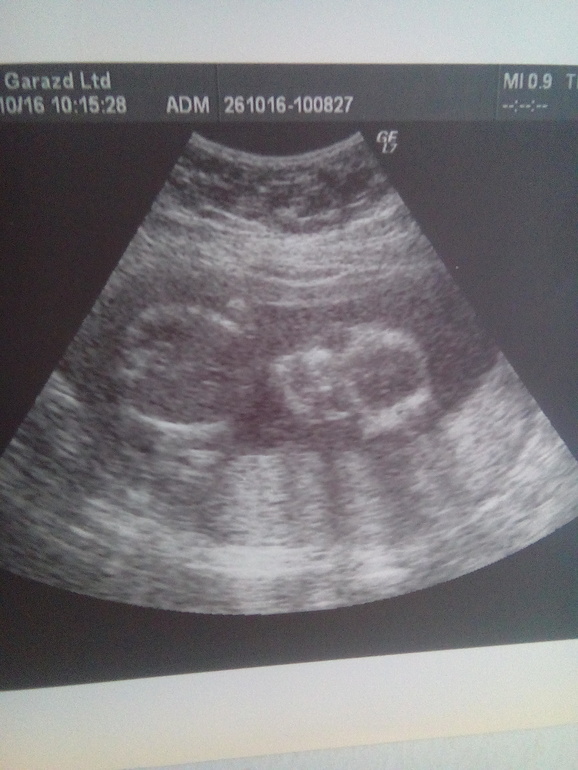

В целом Узи мне понравилось все рассказали показали нафоткали)Соответствует сроку 17 недель все у нас хорошо только тонус ,но я его не чувствую,ну и однократное обвитие(

И у нас будетМАЛЬЧИК)Мне конечно не верится вдруг куда то денется)

Вот и фото)Гляньте девченки действительно ли мальчик?